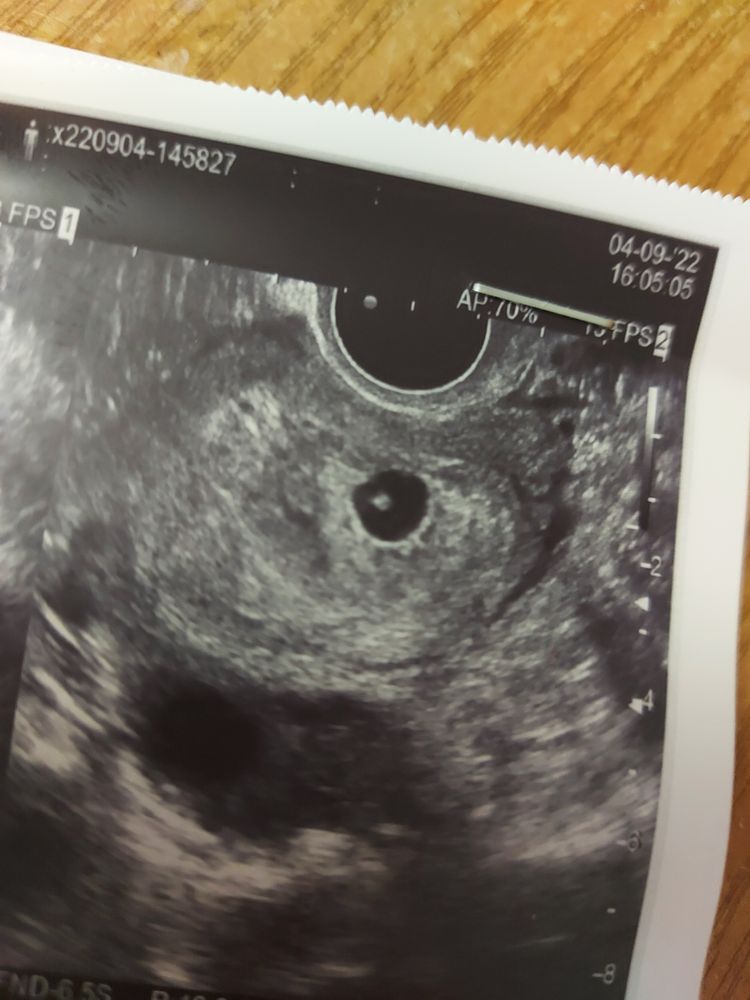

Последние М были 13.07.22 ..Сегодня сделала узи, сказали сердцебиение не слышно, повторить через 2 недели..целый день переживаю, плачу...может у кого такое было?и когда обычно слышно?

Врач может не увидеть сердцебиения и неправильно навести энергетический луч, поэтому и не услышал сердцебиение. Но если размеры плодного яйца и эмбриона соответствуют календарному размеру плодного яйца и КТГ размера, то успокойтесь, все будет хорошо.

При 2-х мм размере эмбриона можно не увидеть сердцебиение. Может быть отсталая техника или невнимательный врач

Alina, сердцебиение должно быть у эмбриона больше 5-7 мм, у вас он просто пока маленький, легко могли и не увидеть. Не переживайте и просто сделайте УЗИ через несколько дней.

Там точка то эта с трудом просматривается, не то что сердцебиение! Все хорошо, у вас же написано «с живым эмбрионом»! Чего ревете? Подождите чуть-чуть.

Т.е. вас не смутило что в результатах написано "и живым эмбрионом"?)))

Сб даже написано есть, нечетко. Собственно с ктр 2 мм четко сложно поймать.

С дочкой на 6 неделях тоже померить не смогли, было просто мерцание.

У вас эмбрион ещё оч маленький, у меня был 1 мм и тоже не услышали, но это нормально . Через неделю уже можно сходить вполне